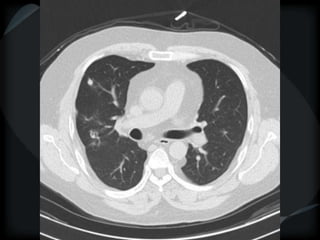

CT features of tuberculosis

 Transbronchial spread – tree-in-bud

 Transbronchial and hematogenous

Tuberculosis

bronchiolitis + hematogenous

TB bronchiolitis + hematogenous